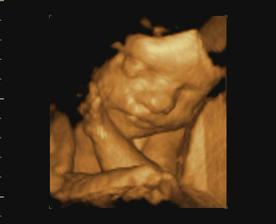

Naše miminko